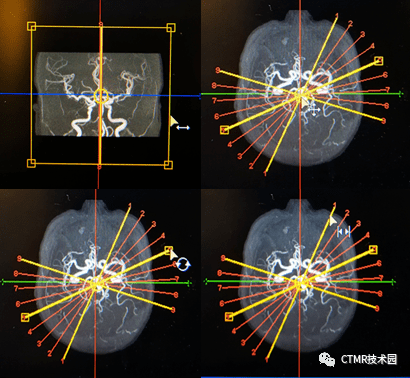

手把手基础教程颅脑3dtofmra扫描及后处理

图片尺寸1080x610